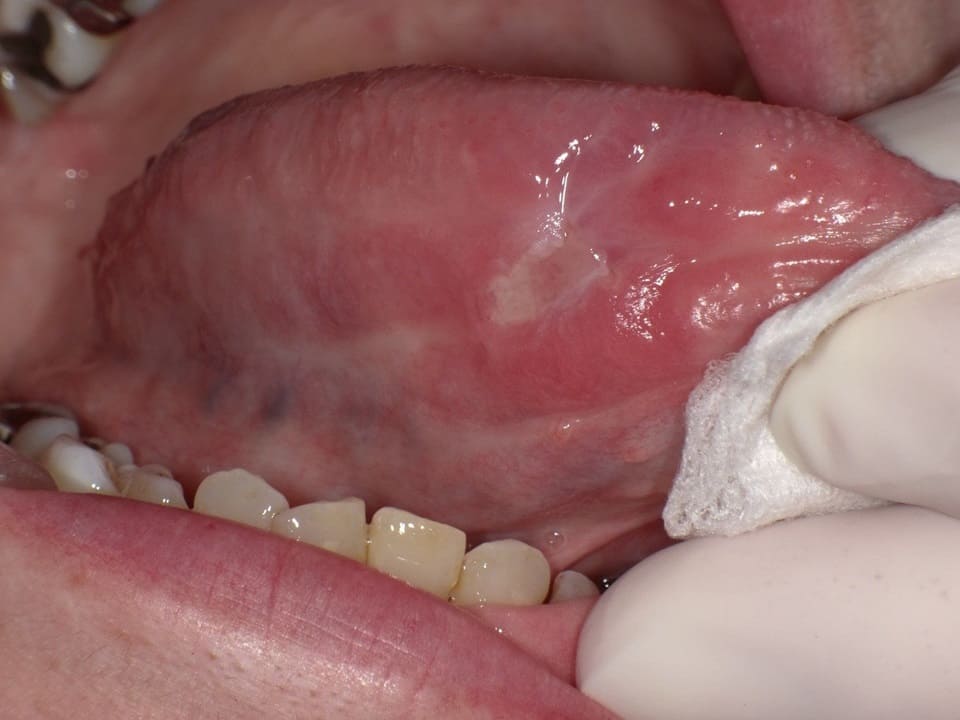

画像 舌がんの初期症状を見逃さないための口内炎との違いとは。

口内炎が痛くない!?舌癌?口内炎?正しい見分け方ハイライフグループ。

舌の口内炎と舌癌はどう違うのか口腔外科医のお役立ちコラム 東京銀座シンタニ歯科口腔外科クリニック。